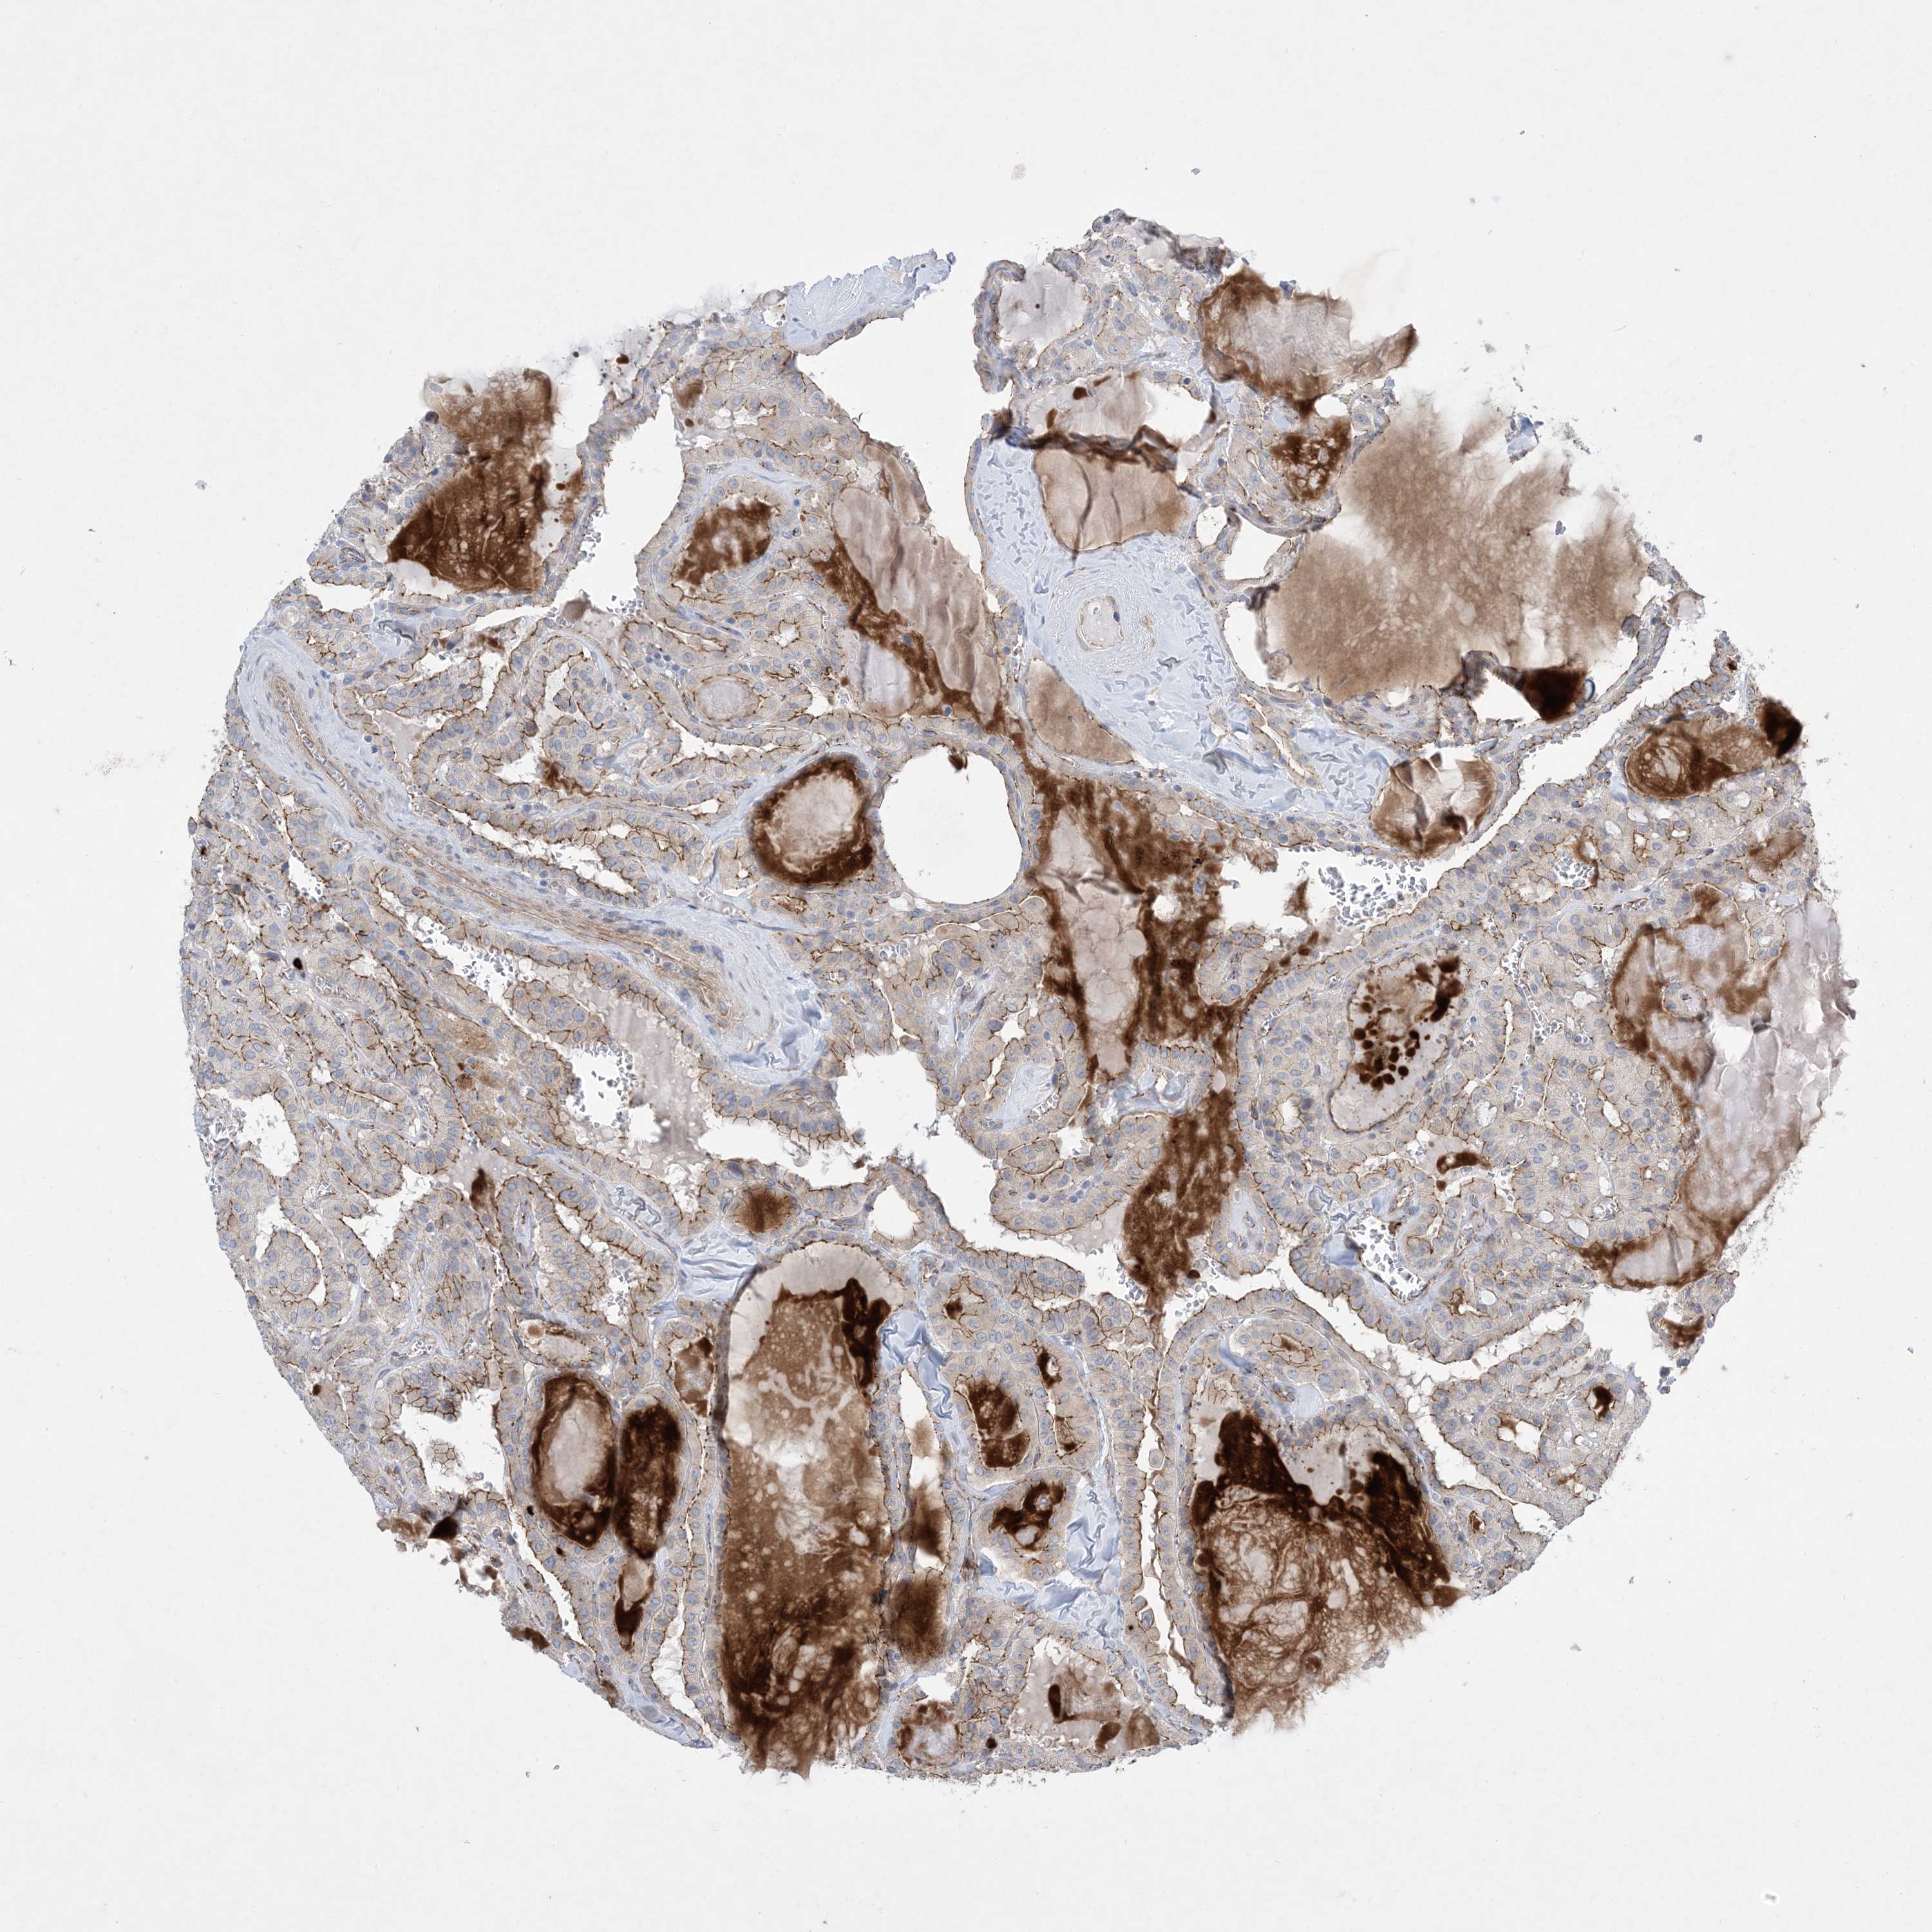

THYROID CANCER - Protein expressioni

A mouse-over function shows sample information and annotation data. Click on an image to view it in a full screen mode. Samples can be filtered based on level of antibody staining by selecting one or several of the following categories: high, medium, low and not detected. The assay and annotation is described here.

Note that samples used for immunohistochemistry by the Human Protein Atlas do not correspond to samples in the TCGA dataset.

Antibody stainingi

Antibody staining in the annotated cell types in the current human tissue is reported as not detected, low, medium, or high, based on conventional immunohistochemistry profiling in selected tissues. This score is based on the combination of the staining intensity and fraction of stained cells.

Each image is clickable and will lead to virtual microscopy that enables deeper exploration of all samples and also displays staining intensity scores, fraction scores and subcellular localization as well as patient and tissue information for each sample.

Antibody HPA035599

Staining

High

Medium

Low

Not detected

Intensity

Strong

Moderate

Weak

Negative

Quantity

>75%

75%-25%

<25%

None

Location

Nuclear

Cytoplasmic/membranous

Cytoplasmic/membranous,nuclear

Papillary adenocarcinoma, NOS

Follicular adenoma carcinoma, NOS